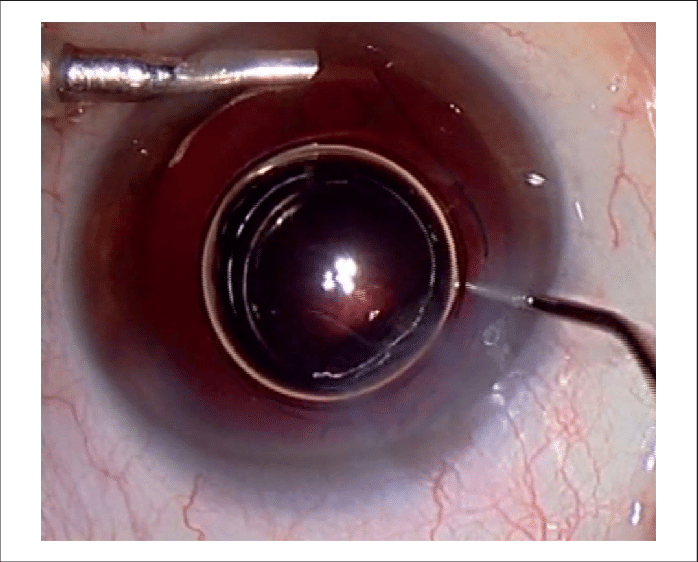

이때 전방에 공기를 주입하여 공기로 전방을 재형성 하거나 (air injection into AC)

Viscoat 와 같은 점탄물질을 이용해서 전방을 형성해주어야합니다.(Viscoat injection)